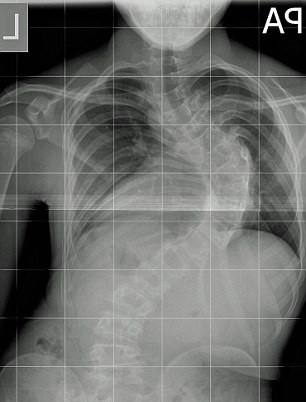

Un adolescent a crescut 12 centimetri peste noapte, dupa o operatie pe care a facut-o la coloana vertebrala.

Harvey Legge, 14 ani, sufera de scolioza, iar curbura cloanei sale era atat de mare, incat ii atingea organele vitale.

Mama copilului spune ca operatia a insemnat un miracol: “Nu pot sa cred… Copilul meu s-a inaltat peste noapte cu 12 centimetri. Este minunat ce s-a intamplat. Este o minune Dumnezeiasca.... ”.

Miracolul despre care povesteste mama baiatului se vede si in radiografiile facute inainte si dupa operatie.